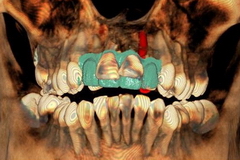

治療前のエックス線

治療前のエックス線

歯根が吸収していて残せない状態でした

審美的に問題がありました。

診査診断が極めて重要です。

インプラントの位置や角度、深さなどを決定します。